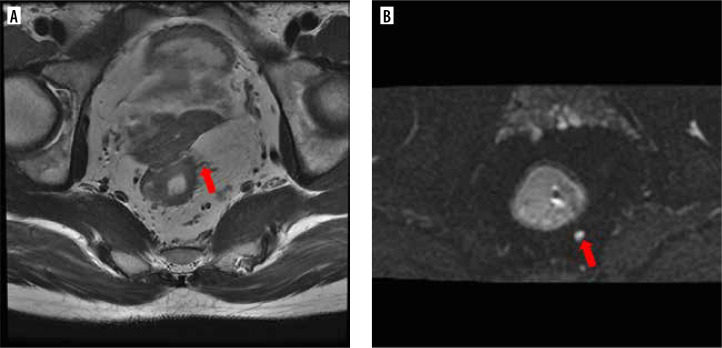

Results: 150 patients were included. Among them, 50 (33.3%) presented with vascular tumour thrombus, and 72 (48.0%) had lymph node metastasis. The detection of regional lymph nodes (DWI-LN) was an independent risk factor for lymph node metastasis. The area under curve of the nomogram model was 0.804.

Conclusion: Preoperative serum CA19.9, and the relationship between tumour and peritoneal reflection in preoperative MRI and DWI-LN have clinical value in predicting lymph node metastasis in patients with rectal cancer.